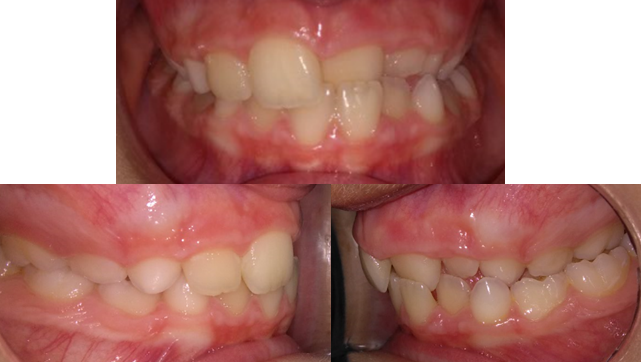

El siguiente caso es muy frecuente en la consulta del ortodoncista. A esta niña de 7 años la trajo a la clínica dental su madre porque le preocupaba la posición de los dientes de sus hija y hacían que la sonrisa no le resultase agradable.

En una primera exploración clínica se observó que la paciente presentaba una mordida cruzada completa en lado izquierdo, incluyendo los dos incisivos o "paletos" izquierdos. Efectivamente la estética de la sonrisa estaba afectada, pero afortunadamente a la niña eso le daba igual y no paraba de bromear y sonreir durante la primera cita. El doctor le recomendó a la madre iniciar el tratamiento de ortodoncia, no por el problema estético, sino por el problema de crecimiento que posteriormente se explicará. Como en todos los casos se realizó un estudio cefalométrico, incluyendo modelos de estudio, radiografía panorámica y telerradiografía.

Foto 1: Inicio del tratamiento.

Tras el estudio se llegó a la conclusión de que problema que presentaba la paciente era sólamente la compresión severa del maxilar superior(lo que comúnmente se conoce como paladar estrecho). Eso era lo que provocaba la mordida cruzada y el apiñamiento severo de la arcada superior.